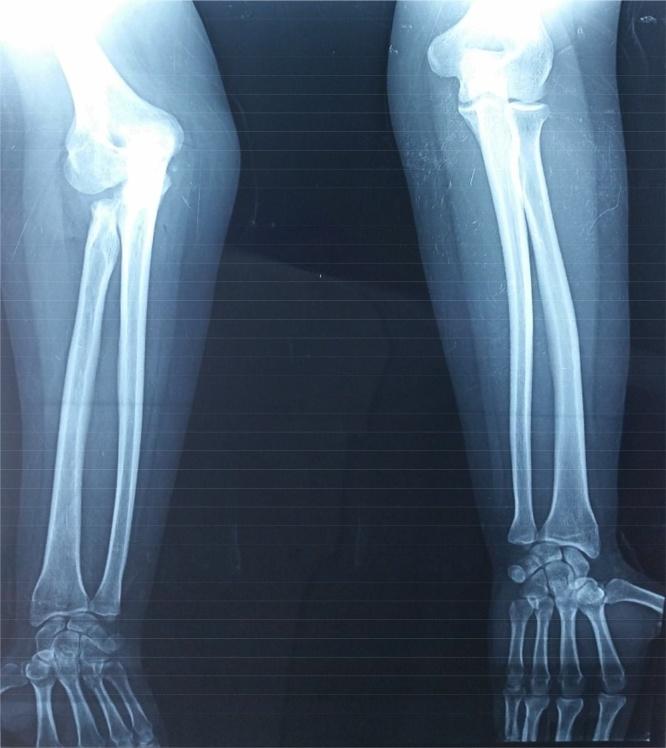

We hereby present the case of a road accident victim, who received a radial head excision for an isolated fracture of the radial head and complicated by onset of cubital tunnel syndrome. This outcome could be the consequence of an iatrogenic valgus of the elbow due to excision of the radial head. Hitherto the surgical treatment of choice it is gradually been abandoned due to development of radial head implant arthroplasty. However, this management option is still being performed in some rural centers with low resources.

The radial head plays an important role in the stability of the elbow and his iatrogenic deformity can be complicated by cubital tunnel syndrome.